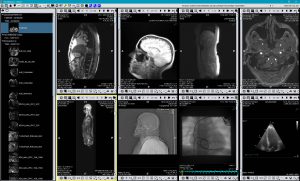

TM-PACS

Le PACS permet la compression, la sécurisation, le stockage et la visualisation d'images radiologiques avec des outils d’affichage et de visualisation pointus (zoom, loupe, annotations, mesure de distance, suivi de mesures, etc.). L’utilisateur peut visualiser à la fois des images coronarographiques, des images PET de médecine nucléaire, ainsi que de l’imagerie plus classique (IRM, CT scan, échographie, etc.). L’utilisation de labels associés aux examens permet de constituer des groupes d’examens et d’y accéder au moyen d’un simple clic. Un système de recherche personnalisée permet de retrouver le dossier du patient ou l'examen désiré de manière très rapide. L’affichage est quant à lui optimisé afin de permettre un affichage multi-écrans sans oublier l’intégration des logiciels RIS et PACS, installés sur les mêmes stations de diagnostic.